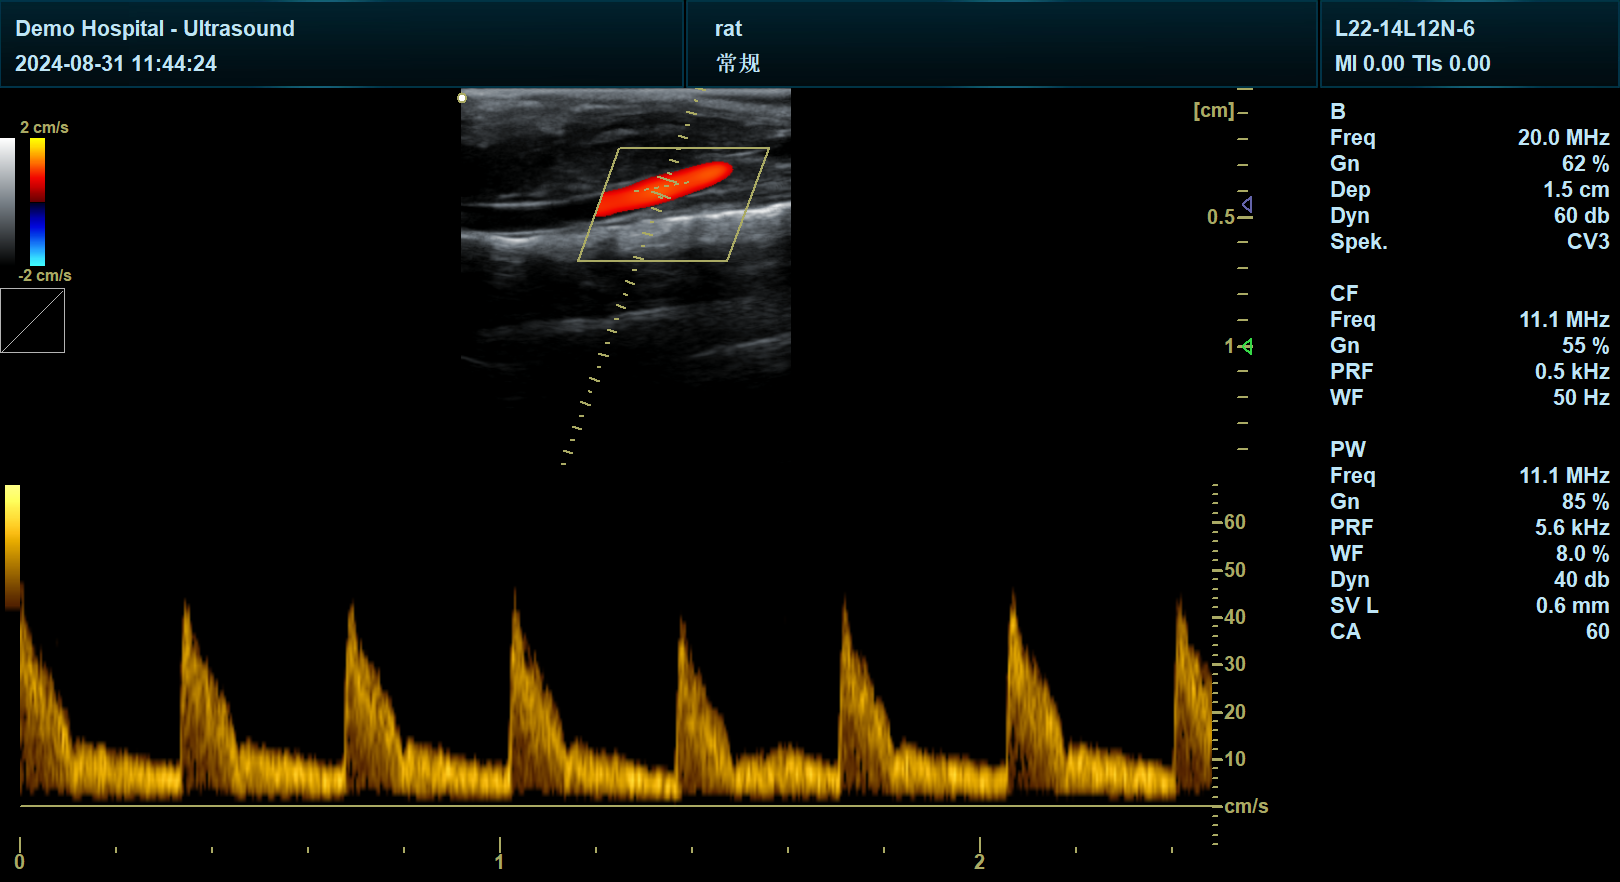

宜慧康科研彩超支持B超、彩色多普勒、频谱多普勒、脉冲组织多普勒、3D/4D成像、弹性成像、造影成像等八大核心模式,并配备多频段探头矩阵(从5MHz腹部探头到18MHz血管探头),可覆盖从腹部大器官到浅表小器官、从成人到儿科的全场景诊断需求。例如,在新生儿先天性心脏病筛查中,其高频探头可清晰显示动脉导管未闭(PDA)、房间隔缺损(ASD)等微小缺损,结合彩色多普勒量化分流速度,为早期干预提供依据;而在肥胖患者肝脏检查中,其低频凸阵探头可穿透厚腹壁,清晰显示脂肪肝分布及纤维化程度。